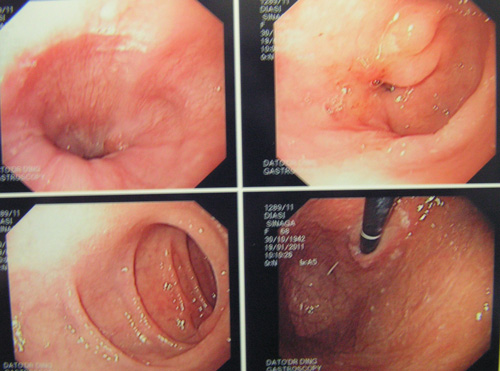

- An upper endoscopy done on the same day indicated gastritis and gastric polyps.